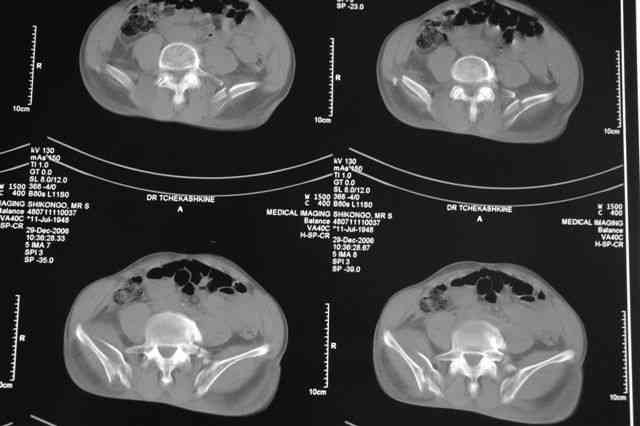

Я помню технику транссакральной фиксации тазового кольца длинными 5 мм Шанцами - повреждения типа В, в этом же случае задний отдел тоже вовлечен

т.е комбинированная нестабильность, поэтому вопрос - достаточно ли только двух Шанцев для стабилизации таза? Что вы думаете об anterior Right SI joint plating + tension band plating from the back.?

Элегантная фиксация, поздравляю.Но ваш случай : одноплоскостная горизонтальная нестабильность Tyle B2.2 отличен от представленного мной - у

моего больного + вертикальная нестабильность за счет повреждения правого крестцово-подвздошного сочленения и перелома заднего отдела подвздошной

кости- С2 тип. Поэтому и возникла дилемма : выбор оптимальной фиксации заднего отдела:

По-поводу фиксации таза спонгиозными винтами. Данный способ все-таки показан для фиксации повреждения крестцово-подвздошного сочленения или переломов крестца. Мне кажется, что в данной случае ситуация иная - имеется перелом "основания" крыла подвздошной кости (в который вовлечена и поверхность, составляющая крестцово-подвздошное сочленение). Не уверен, что фиксация данного повреждения (и заднего полукольца) винтами будет стабильной, так как именно на уровне 1-2 крестцовых позвонков (где обычно вводят винты) линия перелома уходит в латеральном направлении от крестцово-подвздошного сочленения.

PI>По-поводу фиксации таза спонгиозными винтами. Данный способ все-таки показан

для фиксации повреждения крестцово-подвздошного сочленения или переломов крестца. Мне кажется, что в данной случае ситуация иная - имеется перелом

"основания" крыла подвздошной кости (в который вовлечена и поверхность, составляющая крестцово-подвздошное сочленение). Не уверен, что фиксация данного повреждения (и заднего полукольца) винтами будет стабильной, так как

именно на уровне 1-2 крестцовых позвонков (где обычно вводят винты) линия перелома уходит в

латеральном направлении от крестцово-подвздошного сочленения.

Я просмотрел томограммы и у меня создалось впечатление, что винтам есть за что *зацепиться*. В сочетании с 5 мм Шанц винтами, проведенными через нижне-переднюю ость спереди назад через КП сочленения -стабильность тазового кольца должна восстановиться. - Это , конечно, при условии , что закрытая рнепозиция будет успешной.

Травма произошла 22 или 23 декабря, ко мне больной попал 26 декабря, 3 января -остеосинтез перелома бедра и внутр.лодыжки.

после КТ отказался от этой идеи - двусторонний перелом крестца в зоне 1 - алярная часть, при попытке низведения правого гемипелвиса теоретически есть вероятность смещения

фрагмента крестца слева.